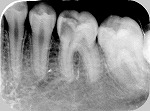

◆根管治療

むし歯等で歯の神経が死んでしまった場合に必要となる根の治療です。

根管治療X線写真